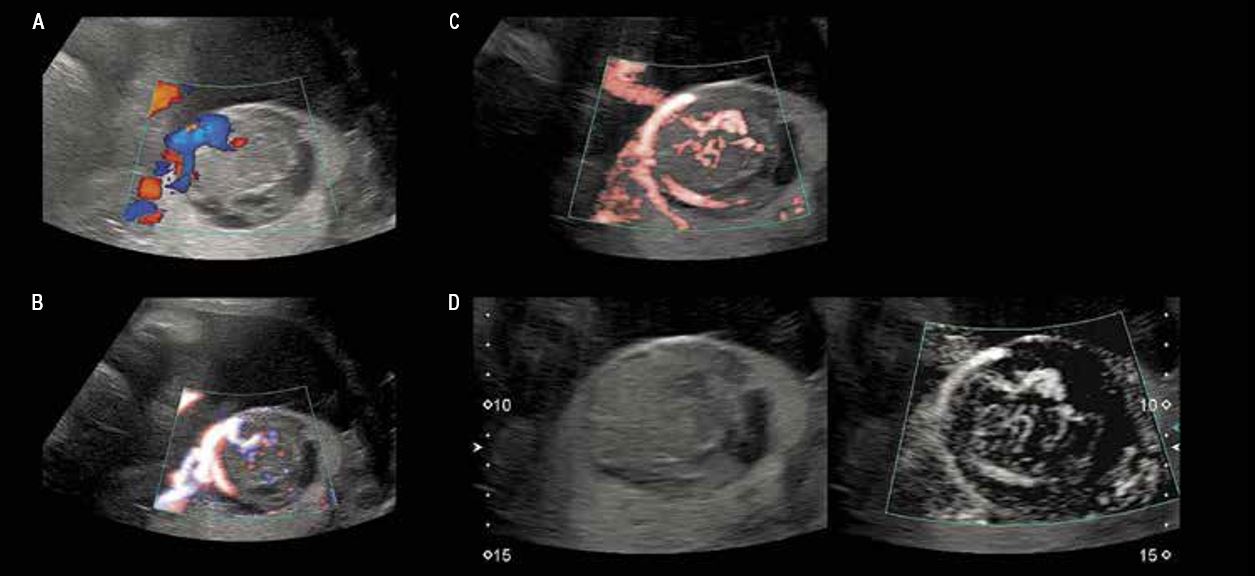

Хоріоангіома плаценти (мал. 3)

Хоріоангіома плаценти – це патологічне розростання кровоносних судин у субхоріонічній частині плаценти, що складається з численних дрібних капілярів у міксоїдній тканині. Великі хоріоангіоми можуть ускладнюватися водянкою плоду та внутрішньоутробною загибеллю плоду. Небезпека збільшується при екстенсивному кровопостачанні, оскільки це провокує розростання ураженої ділянки та приводить до ефекту «обкрадання». Навпаки, через значні некротичні зміни небезпека ускладнень зменшується. Моніторинг плода адаптований відповідно до цих умов.

Мал. 3. Гетерогенне ураження субхоріонічної плаценти поруч із місцем прикріплення входженням пуповини до плаценти:

A, B — при звичайному допплерівському картуванні видно лише найбільші артерії та вени;

C, D — ідентифікація кровотоку в мікросудинах у ураженій ділянці з використанням методу SMI підтверджує діагноз і уможливлює оцінку ризику гемодинамічної декомпенсації, а також виявлення зон із поганим кровопостачанням та некротичних зон.

Субхоріальна гематома (мал. 4)

Субхоріальна гематома, яка в деяких випадках може бути дуже великою, це порівняно звичайне явище, яке не свідчить про якусь значну патологію. Повна відсутність кровопостачання, підтверджена відсутністю сигналу під час УЗД за технологією SMI, виключає діагноз хоріоангіоми і, отже, небезпеку гемодинамічних порушень. Утворення гематоми та її подальша реабсорбція призводять до виникнення субхоріальної кісти.

Мал. 4. Диференційна діагностика: субхоріонічна гематома